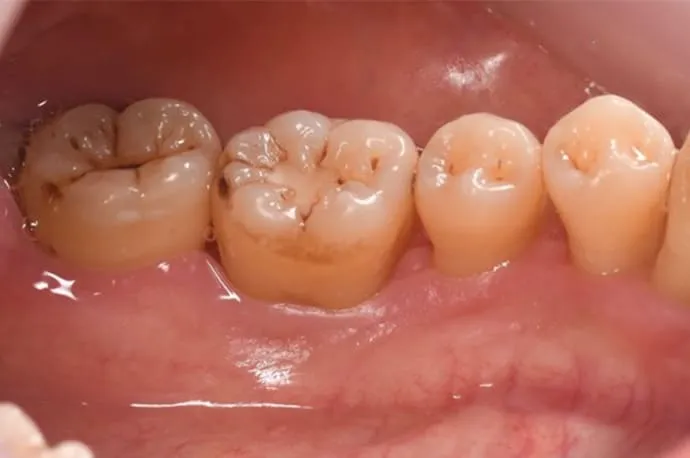

治療前

治療後

歯周基本治療後の状態です。治療により歯ぐきの腫れや出血が改善し、炎症が落ち着いている様子が確認できます。歯石の除去によって、口臭やお口の中の不快感も軽減しています。

※歯周病によって歯ぐきが腫れていた場合、炎症が治まることで歯ぐきが引き締まり、治療前より下がったように見えることがあります。

※歯石除去後、一時的に知覚過敏の症状が出る場合があります。